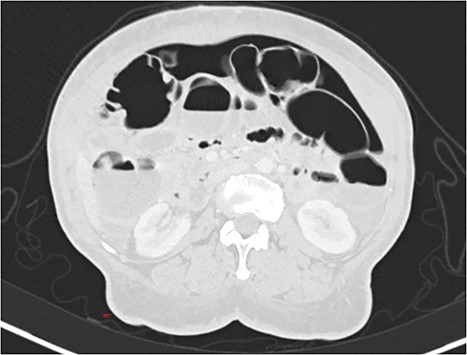

A 55-year-old woman was being followed in a gynecology consultation for a large abdominal mass, likely of adnexal origin (370 mm in its largest dimension). She underwent a hysterectomy, bilateral adnexectomy, and segmental enterectomy due to an iatrogenic perforation of a small bowel loop. On the seventh postoperative day, due to the absence of intestinal transit since surgery, an abdominal X-ray was requested, and general surgery was consulted, suspecting pneumoperitoneum. In this context, the patient underwent a CT scan, which revealed “pneumoperitoneum in the free cavity, significant for one week postoperative, with about 4 cm anteroposterior diameter in the epigastric region. There is also a significant amount of retroperitoneal air in the left pelvic cavity, extending to the presacral space. There are no gas bubbles immediately adjacent to the surgical suture lines.” (Figs 3 and 4). Blood tests showed no significant alterations, and clinically, the patient was hemodynamically stable with only mild tenderness on abdominal palpation, without guarding. Based on the clinical, laboratory, and imaging findings, it was decided to keep the patient on a nil-by-mouth diet with clinical observation. The next day, the patient resumed intestinal transit, allowing for the reintroduction of an oral diet. Blood tests showed no increase in inflammatory markers. The patient continued to progress favorably during the remainder of her hospital stay and was discharged on the tenth postoperative day.